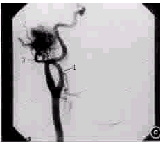

4例乳突X线摄片,1例示颞骨鼓部骨质破坏,1例未见明显骨质破坏,2例示乳突及外耳道后骨壁骨质破坏。5例行CT检查:1例鼓室明显扩大,鼓室前壁及颈静脉球窝前壁骨质破坏。岩锥骨质破坏4例,其中2例为岩锥内占位性病变分别为3 cm×2 cm×2 cm及3 cm×3 cm×2cm软组织影,并破坏岩锥前壁突入中颅窝;颈内静脉球受压移位或消失各1例,其中移位的1例同时行磁共振成像(magnetic rasonance imaging,MRI)、磁共振血管成像(magnetic rasonance artery,MRA),MRI示右侧颈内静脉球窝处见一类圆形肿块,边界清,约3 cm×2 cm×2 cm,MRA示右颈内静脉球区有异常血管团,右颈内动脉近颅段轻度向左移位,动脉造影示35 mm×32 mm团块影,供血丰富,主要由颈外动脉的颞浅及颌内动脉支供血(图1)。

图1 患者女,39岁,右耳肿物。a MRI示右侧颈内静脉球窝处类圆形肿物3 cm×2 cm×2 cm,边界清;b 右颈总动脉造影正位片见一35 mm×32 mm团块影,血供丰富;c 右颈总动脉造影侧位(30°)片,①颈外动脉,②颞浅动脉,③颌内动脉,肿瘤的主供血管